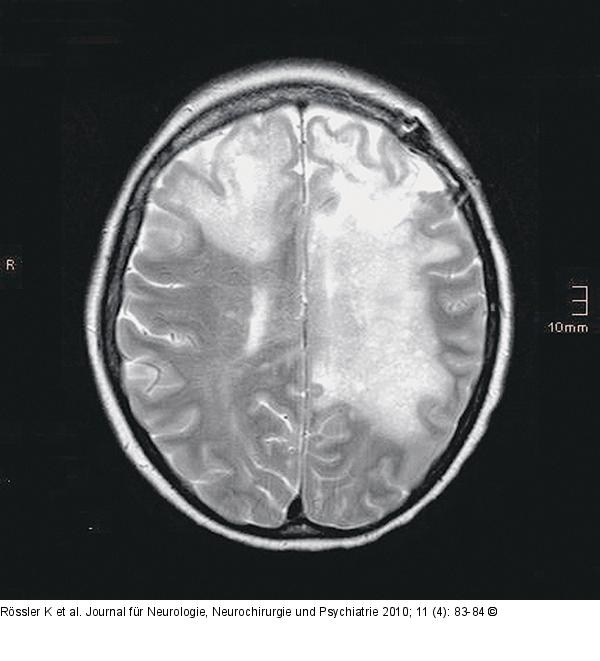

Abbildung 7: Grand-mal-Anfall

MRT, T2, axial: ausgedehntes, bihemisphärisches Ödem. |